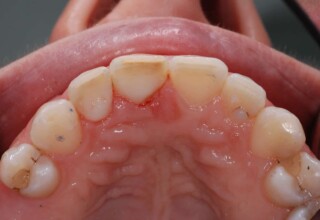

A rare case of dark root canal teeth with additional external absorption on the central incisor. After removal of the affected tissues of the central incisor, the tooth could not be directly bleached because of the soft tissue contact. The tooth was initially restored to provide the original tooth form, then it was bleached and the restoration was finalized.

Initial appearance

Final appearance